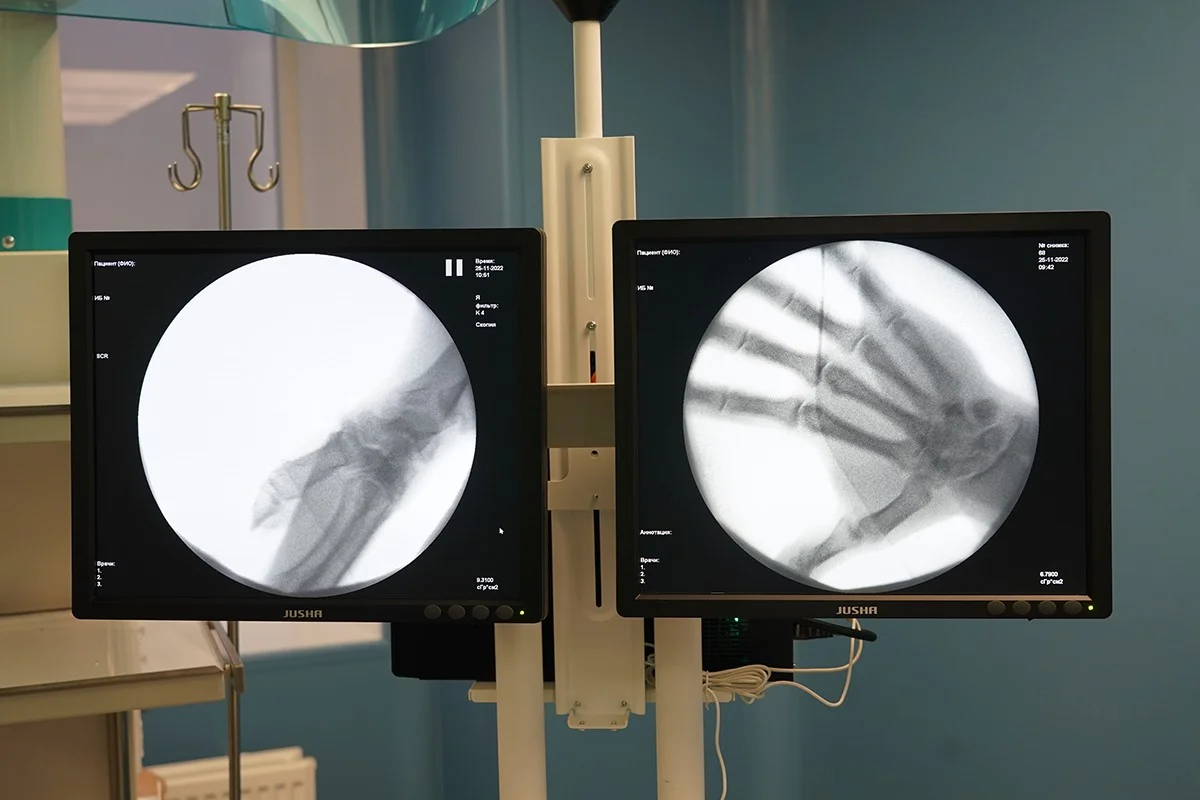

Помимо оперблока участники рабочего выезда осмотрели обновленный травмпункт, в котором также провели капитальный ремонт и закупили еще один рентген-аппарат стоимостью 14,8 миллиона рублей по региональной госпрограмме развития здравоохранения.